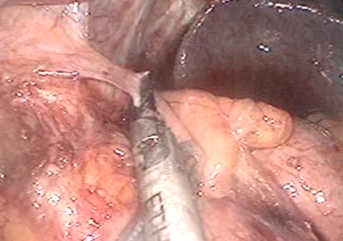

ホチキスを入れた穴を針と糸で縫ってふさぎます。これで完成です。

- 4

胃から食道への胃酸の逆流を少なくするため、胃の壁の一部を食道の壁に縫い付けます。